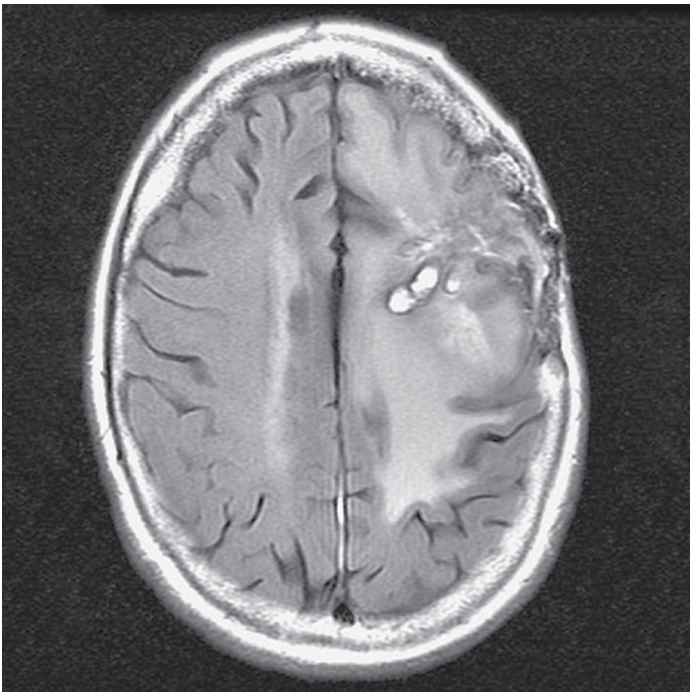

Axial T2-weighted FLAIR of the brain